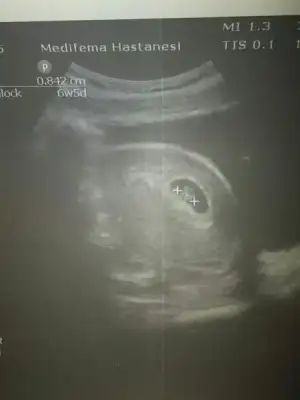

Merhaba cnm benimkinide yorumlarmisin.usg karindan